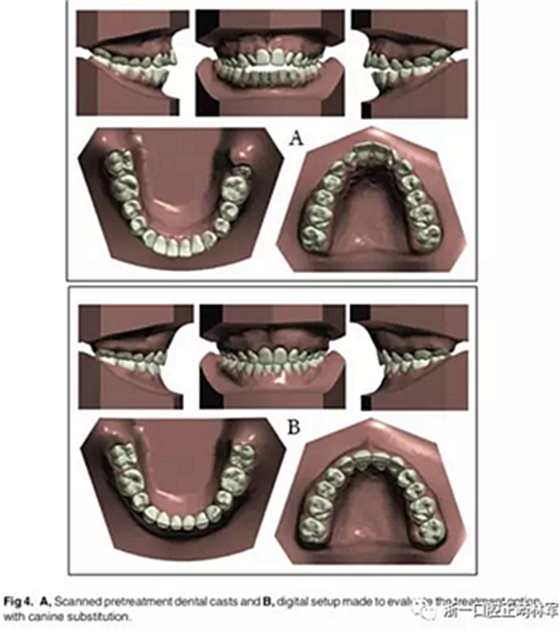

經(jīng)過考慮,選擇方案1拔除上頜側(cè)切牙和下頜第二前磨牙。由于早期牙髓壞死,這些根部的牙本質(zhì)很薄,因此在正畸運(yùn)動過程中上頜側(cè)切牙極易發(fā)生牙根外吸收。同時設(shè)計(jì)上頜尖牙的側(cè)向移動。為了改善診斷方案和治療結(jié)果,考慮到拔牙方式的獨(dú)特性,我們對此病例進(jìn)行了數(shù)字化設(shè)置(圖4)。